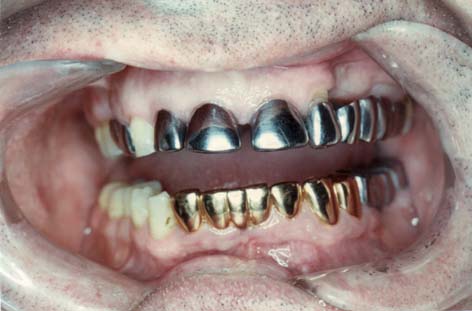

Mehrere Gramm Quecksilber trägt eine mit einer

durchschnittlichen Anzahl von Amalgamfüllungen versehene

Person im Mund.

Amalgamgebiss mit Amalgam in Backenzähnen [1]

Amalgamgebiss

mit

Frontzähnen aus Amalgam [2]